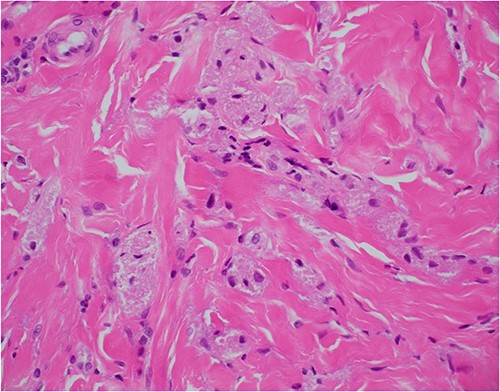

Haematoxylin and eosin stain, 100× magnification, showing tumour cells in stroma that may not be sampled by a superficial biopsy.

Haematoxylin and eosin stain, 400× magnification, showing tumour cell features of nests of epithelioid cells in the stroma with indistinct borders and granular pale eosinophilic cytoplasm.